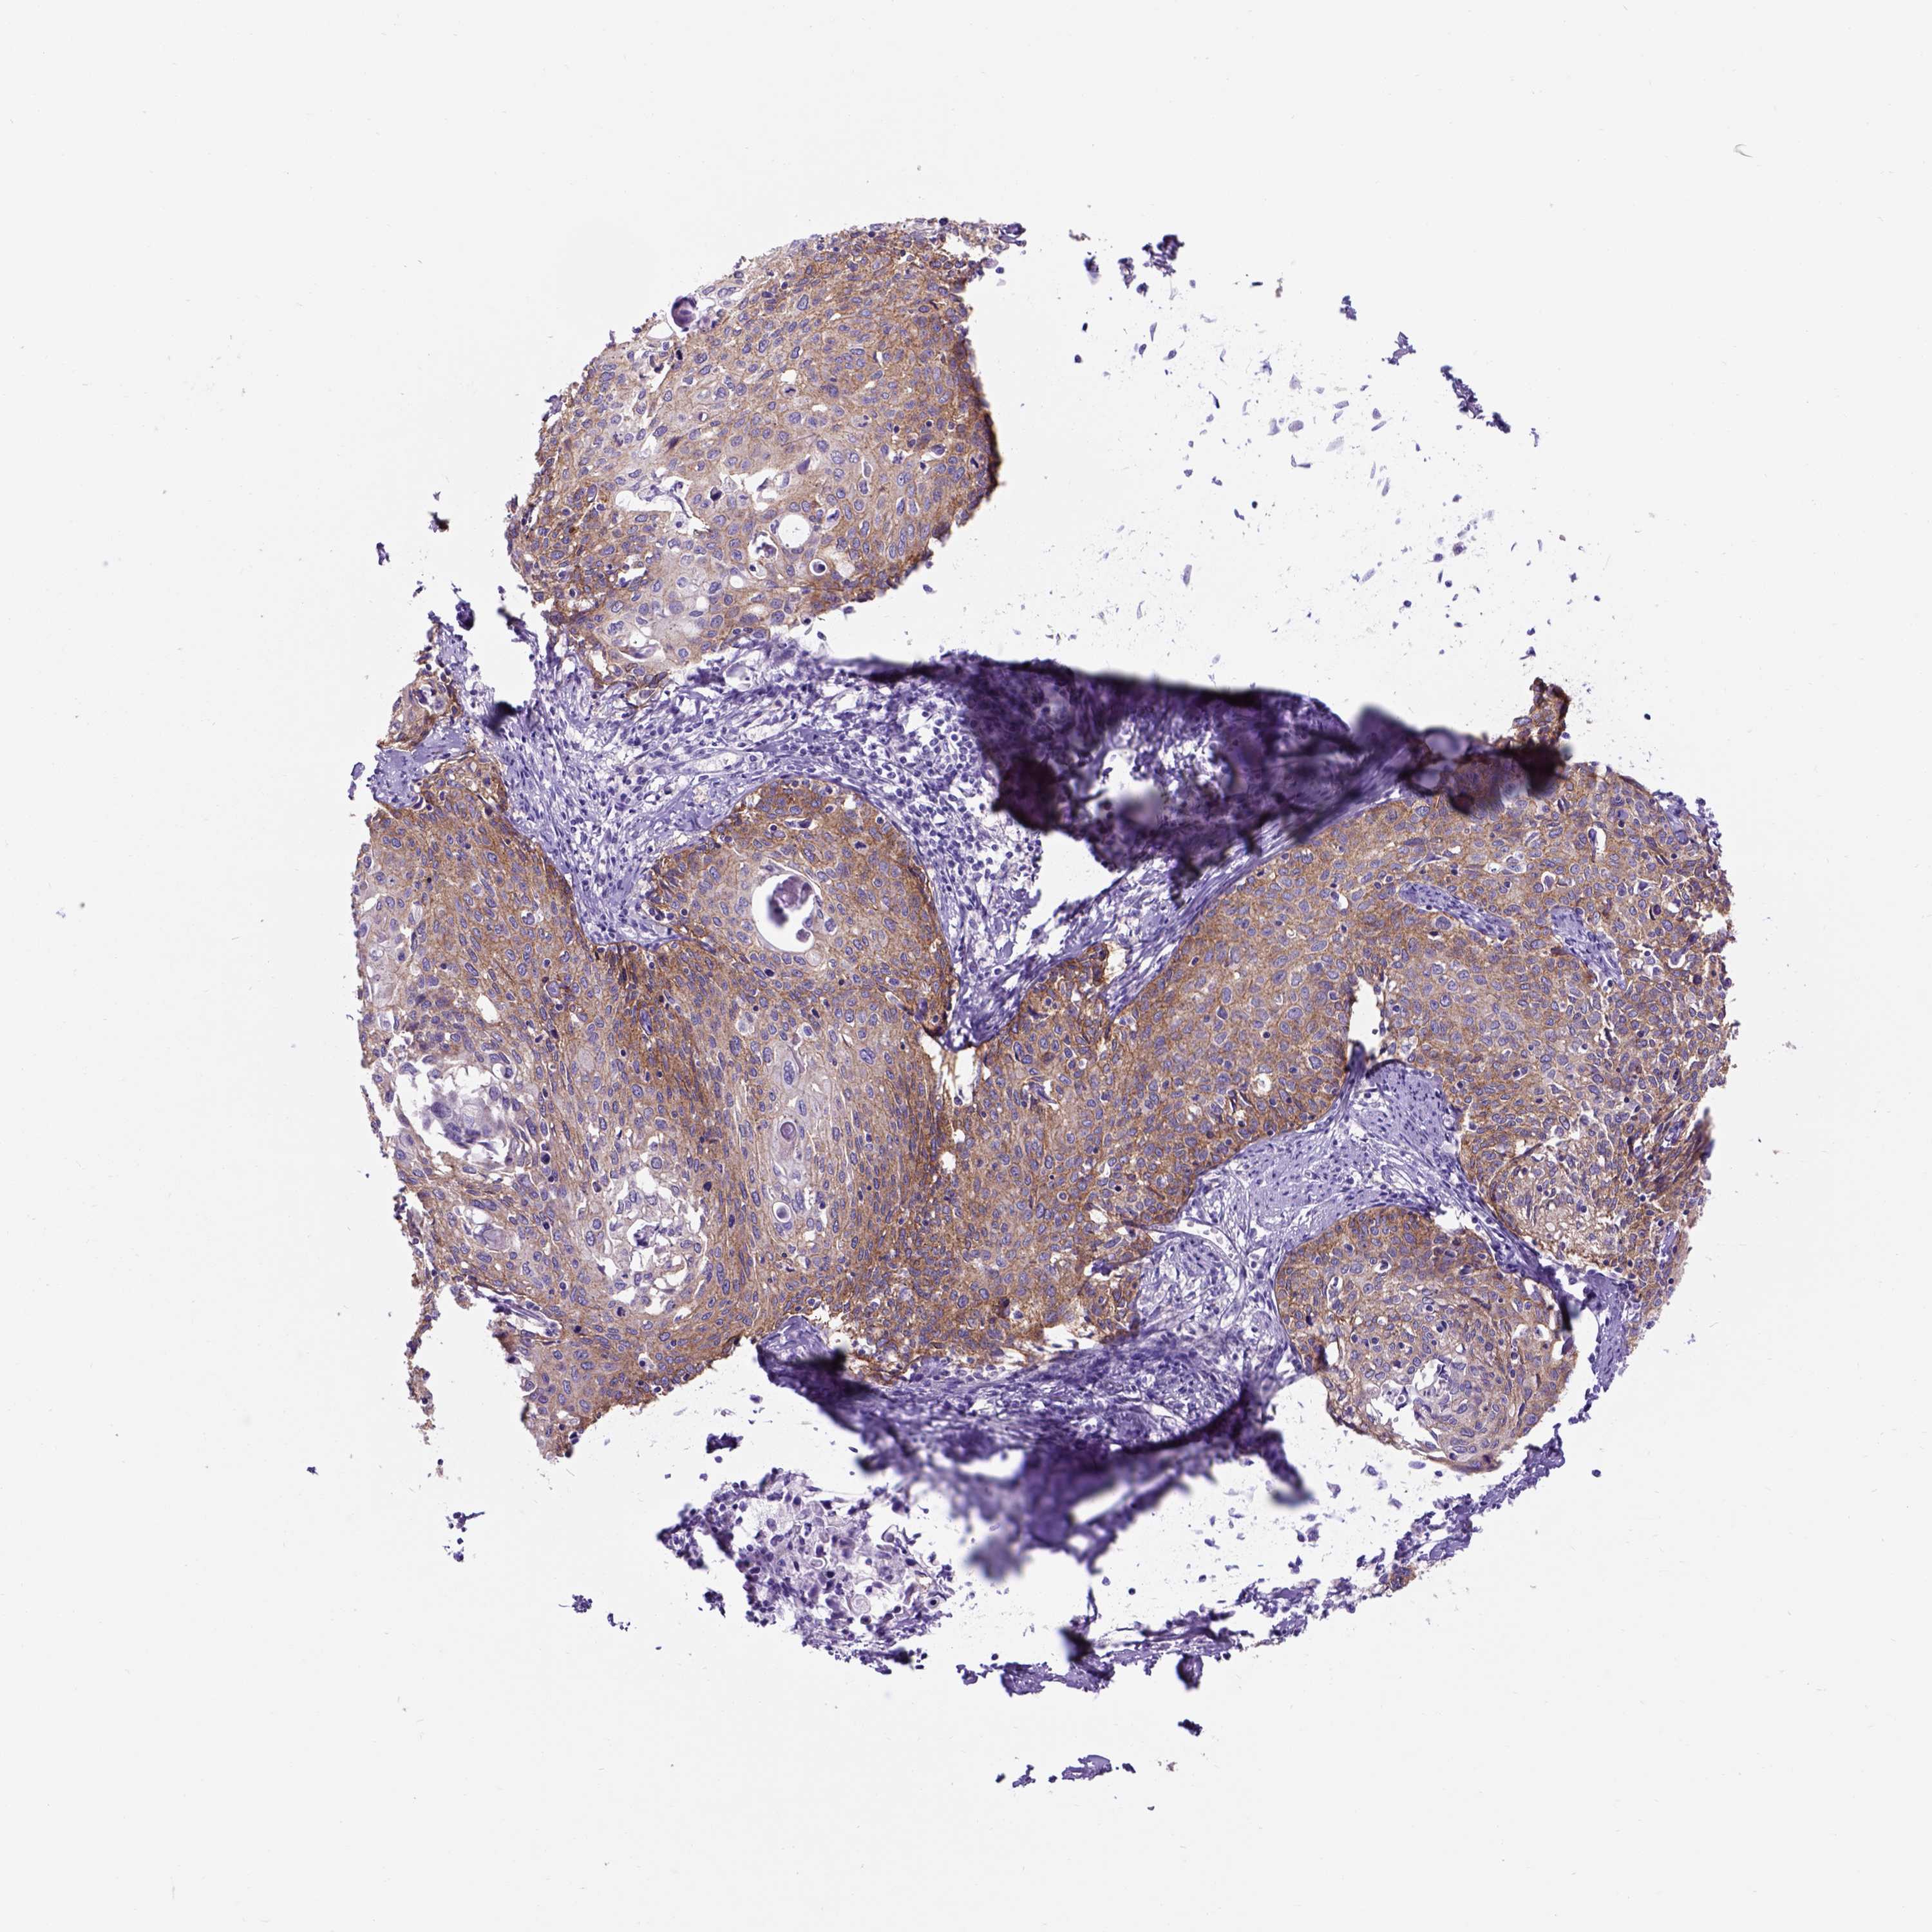

CERVICAL CANCER - Protein expressioni

A mouse-over function shows sample information and annotation data. Click on an image to view it in a full screen mode. Samples can be filtered based on level of antibody staining by selecting one or several of the following categories: high, medium, low and not detected. The assay and annotation is described here.

Note that samples used for immunohistochemistry by the Human Protein Atlas do not correspond to samples in the TCGA dataset.

Antibody stainingi

Antibody staining in the annotated cell types in the current human tissue is reported as not detected, low, medium, or high, based on conventional immunohistochemistry profiling in selected tissues. This score is based on the combination of the staining intensity and fraction of stained cells.

Each image is clickable and will lead to virtual microscopy that enables deeper exploration of all samples and also displays staining intensity scores, fraction scores and subcellular localization as well as patient and tissue information for each sample.

HPA001200

HPA018530

CAB000035

CAB068186

CAB073534

CAB080313

CAB080314

CAB080473

CAB080475

CAB080506

CAB080507

CAB080509

CAB080510

CAB080511

Staining

High

Medium

Low

Not detected

Intensity

Strong

Moderate

Weak

Negative

Quantity

>75%

75%-25%

<25%

None

Location

Nuclear

Cytoplasmic/membranous

Cytoplasmic/membranous,nuclear

Adenocarcinoma, NOS

Squamous cell carcinoma, NOS